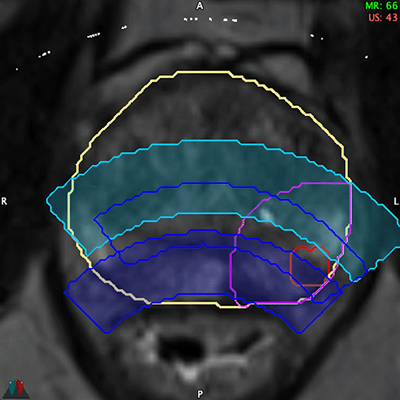

Before the procedure: Identify challenges and choose the optimal treatment modality using MR, PSMA PET Imaging, and 3D ablation energy

models.

In the operating room: Focus on executing the pre-plan.

Complete every procedure with confidence that you delivered the best possible therapy.